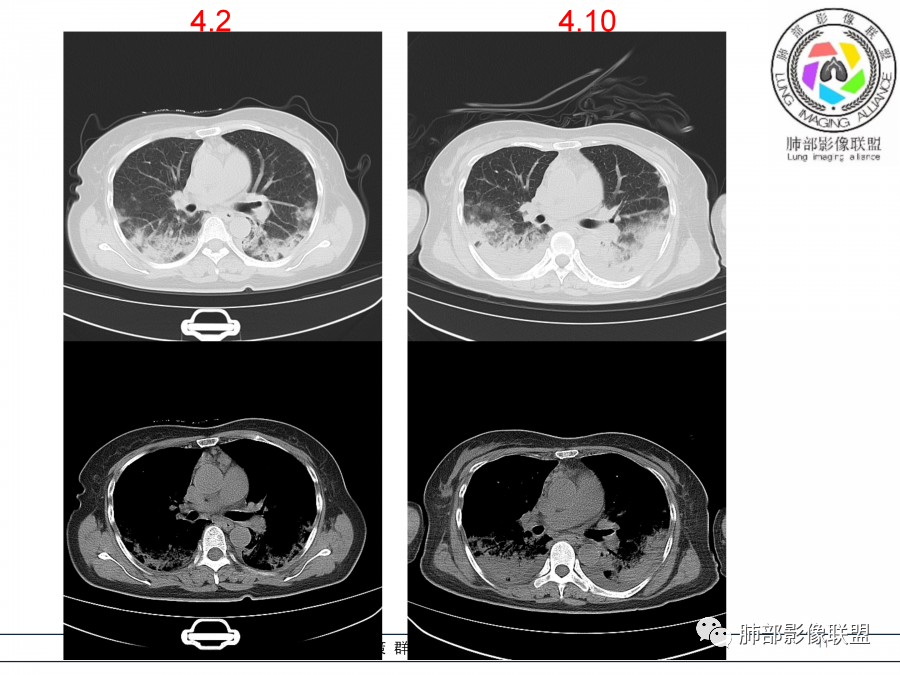

影像,第一次双肺中下叶胸膜下多发斑片状实变影,部分融合成,周围散发磨玻璃影,磨玻璃影内可见小叶间隔及小叶内间隔增厚,病变平行于胸膜,第二次间隔8天,双肺实变影明显进展,有重力作用,支气管近端堵塞,进展较快,临床有发热,血沉高,狼疮SLE阳性,考虑1:OP(机化性肺炎)2:SLE相关肺炎,建议支气管镜灌洗液病原学检测。

老年女性,咳嗽咳痰伴发热7天,白细胞不高,血沉快,降钙素原不高。其他化验未见明显异常,狼疮全套抗Ro/SSA阳性,双肺野靠近胸膜下磨玻璃实变影,支气管通畅,有充气征,沿胸膜下分布,有细网格征,7天后进展明显,实变影加重,胸膜肥厚,胸水不明显,心包少量积液?抗感染治疗无效,考虑非感染性疾病可能性大,结缔组织相关性肺病?狼疮性肺炎?机化性肺炎?鉴别病毒性肺炎。

老年女性,咳嗽咳痰发热7天。无气促。白细胞计数不高,PCT稍高,PPD(+),抗Ro/SSA阳性。CT:双肺野靠近胸膜下磨玻璃实变影,支气管通畅,有充气征,沿胸膜下分布,有细网格征。予抗生素治疗,8天后复查胸部CT见病灶范围扩大,实变影加重,胸膜肥厚,胸水不明显。抗感染治疗无效,考虑有:1.非感染性疾病:结缔组织相关性肺病,支持点:肺部CT表现为间质性炎症病变,抗RO/SSA(52)阳性;2.病毒性肺炎:患者无气促症状,可能性小;3.肺结核。

第一次双肺中下叶胸膜下多发斑片状磨玻璃及实变影,病变平行于胸膜,支气管通畅,8天后,双肺实变影明显进展范围扩大,部分支气管近端堵塞,进展较快,胸腔积液,抗感染治疗无效,考虑:非感染性疾病:结缔组织相关性肺病。鉴别机化性肺炎。